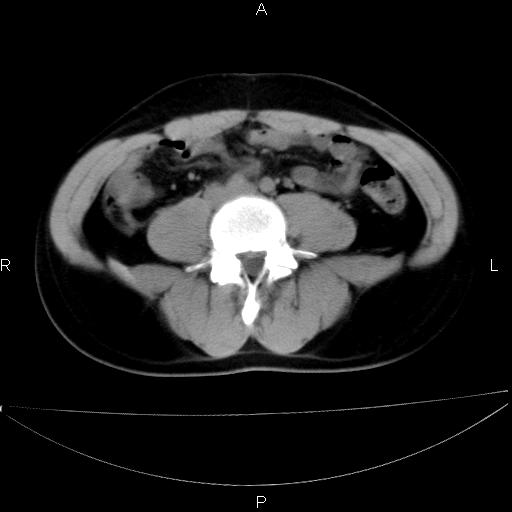

双肾轻度积水,未见明确结石,薄层对结石检出率较高。

要排除upj,可做ivp造影

未见明确输尿管结石,mru效果还好

双侧输尿管上端扩张,未见明确结石,可进一步ivp检查。